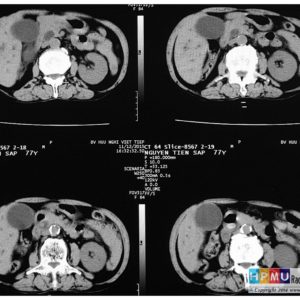

Sỏi đường mật